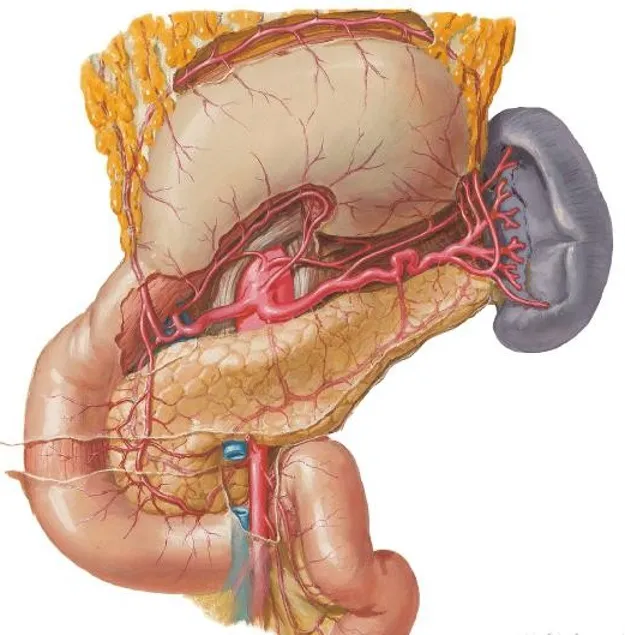

●胰腺的动脉来源与分布是腹部最复杂的器官之一,它不像肝、脾、肾等实质脏器都有其固有的“门”供血管进出,其动脉是围绕胰腺周围分布并相互吻合形成复杂的血管网。总的来看胰腺的动脉来自腹腔干的分支及肠系膜上动脉。

胰头背侧动脉供应

胰腺背面动脉供应

●胰腺静脉回流:

门静脉和脾静脉汇合点正好位于胰颈后方,肠系膜上静脉和脾静脉在此融合形成门静脉。

脾静脉沿着胰体后表面行进至门静脉和脾静脉汇合点(胰腺标识血管)。

●总结:胰腺的动脉血来自腹腔干和肠系膜上动脉的分支,而静脉血则通过肠系膜上静脉或脾静脉回流至门静脉。